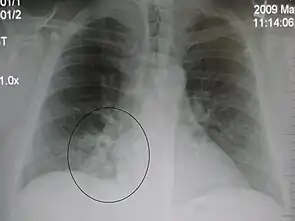

Right upper lobe pneumonia as marked by the circle.- Left upper lobe pneumonia with a small pleural effusion.

- Right lower lobe pneumonia as seen on a lateral CXR